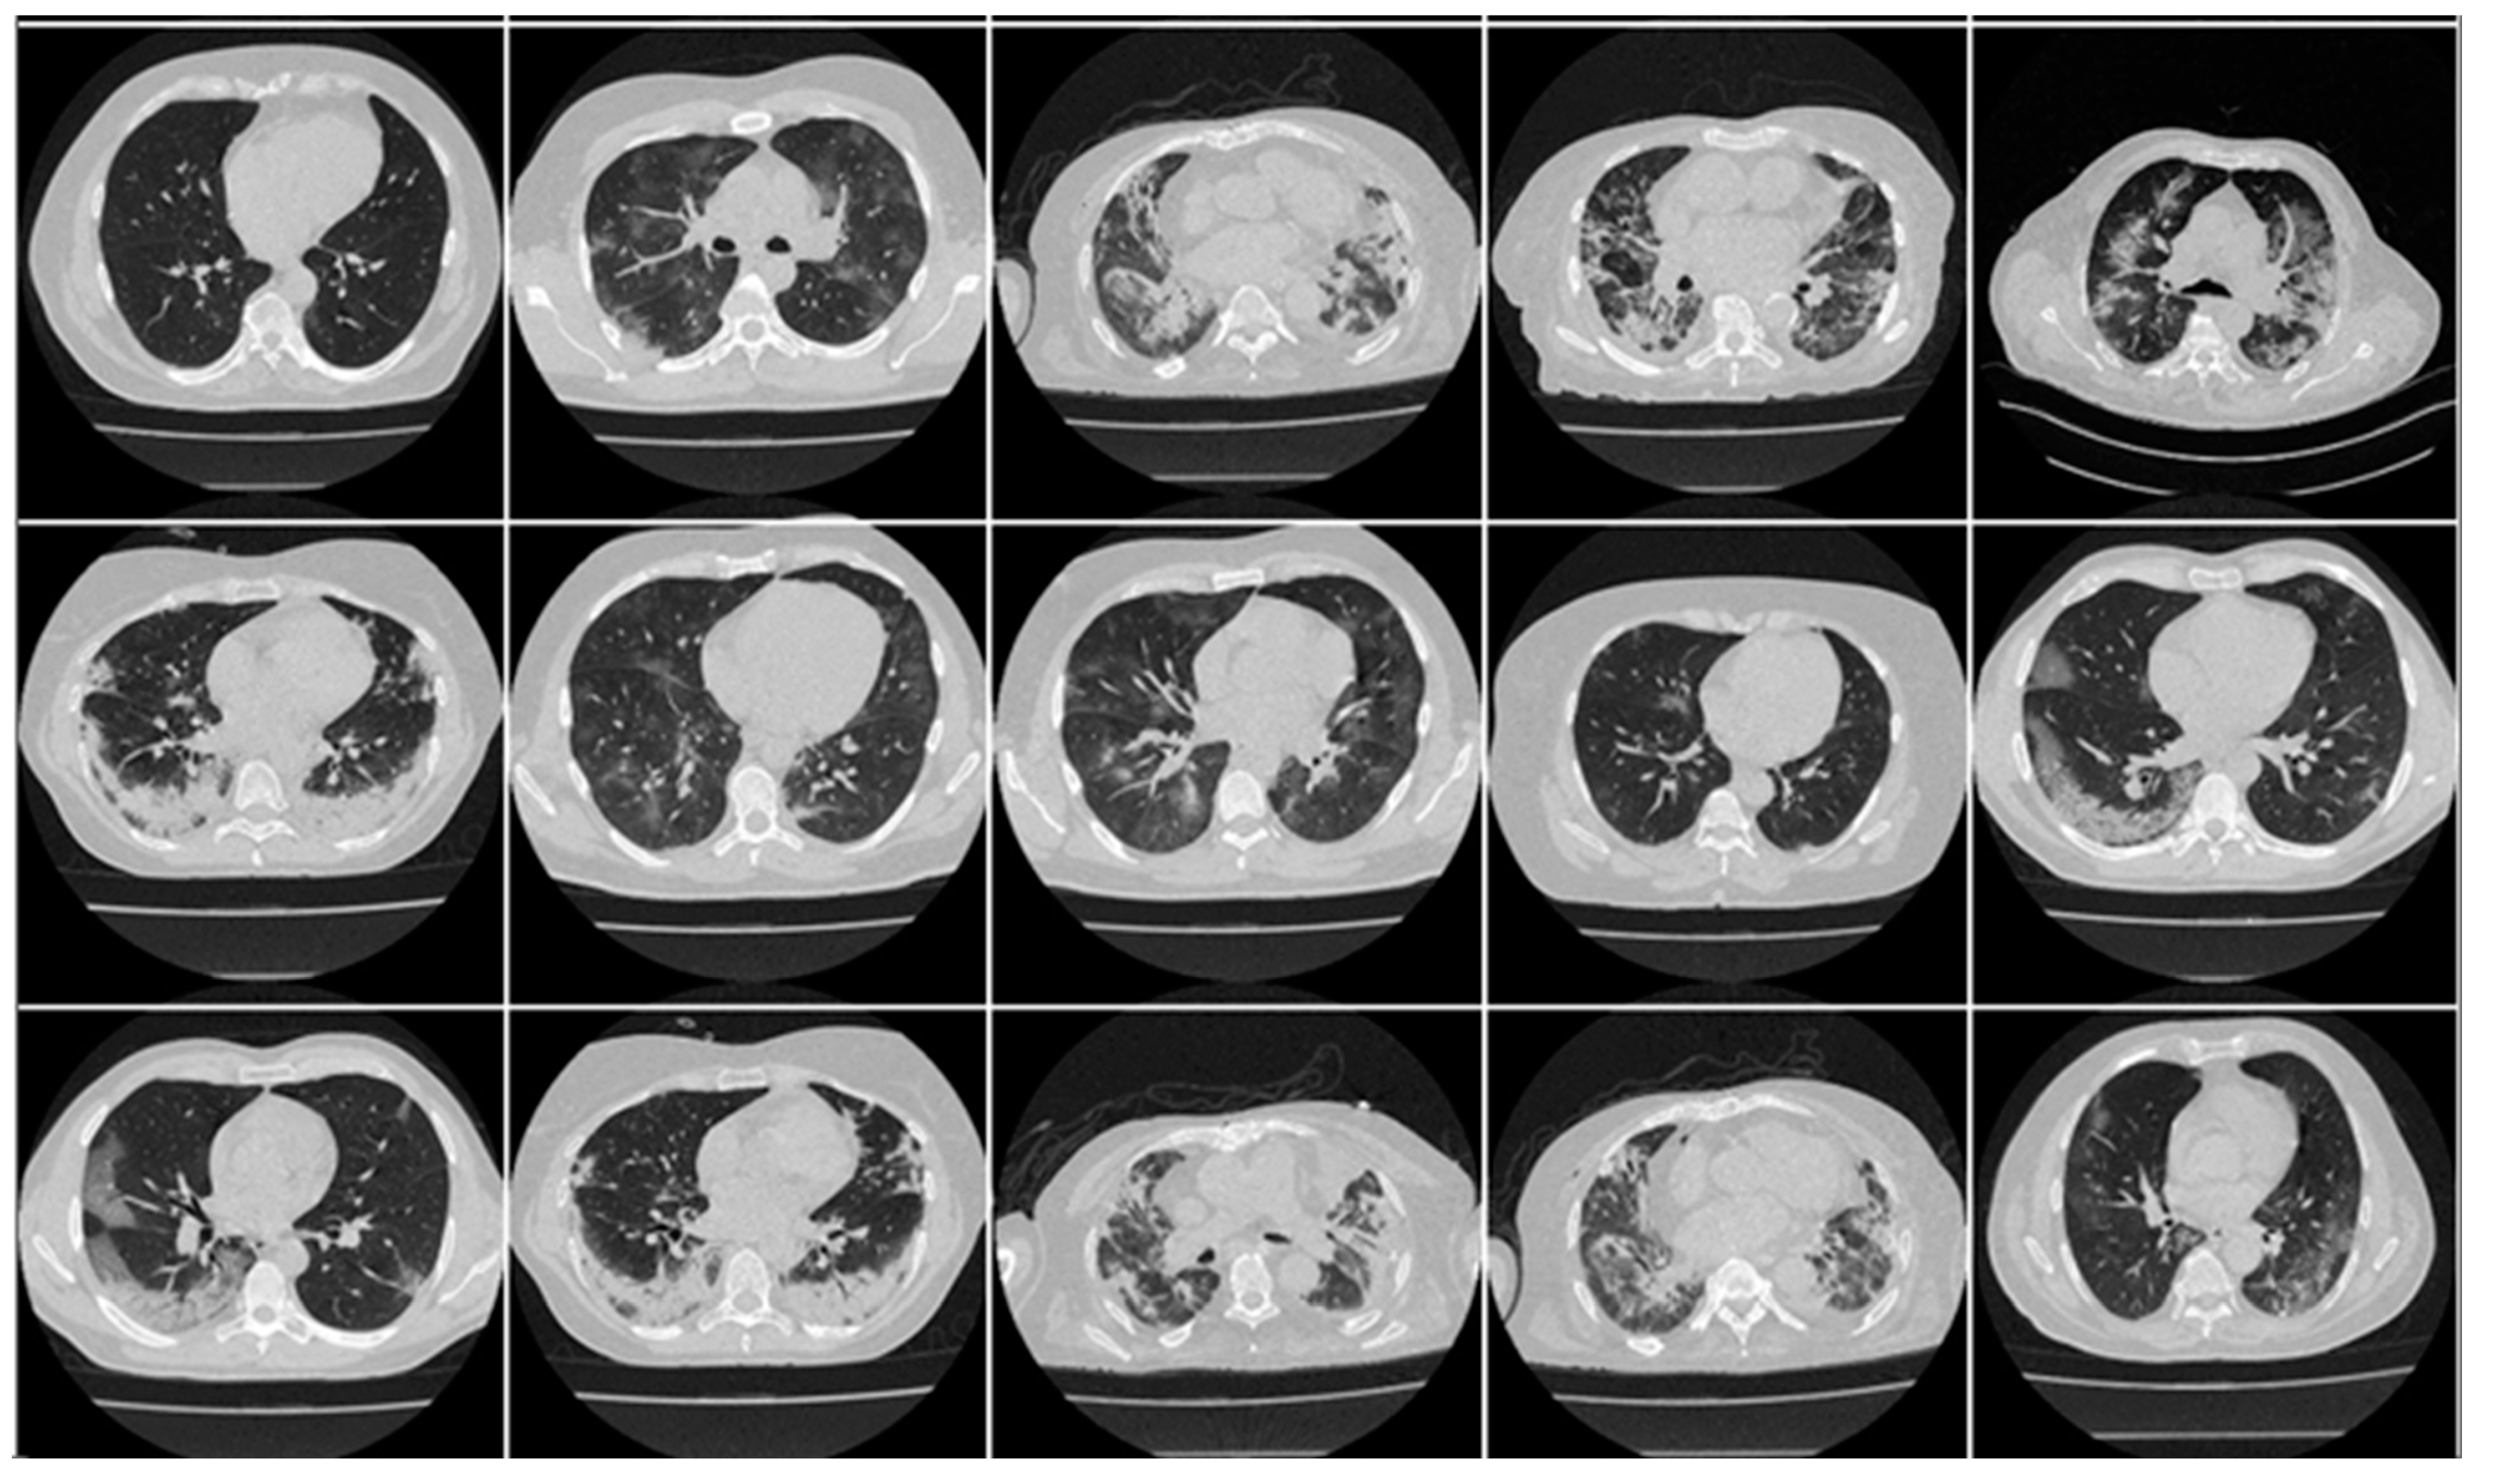

In this research work, we utilized two distinct cohorts from different countries. This dataset has already been validated by radiologists and doctors who are also co-authors in this paper. The first cohort, referred to as the experimental data set, consists of 80 CroMED COVID-19-positive individuals, with 57 males and the remainder female. Sample images are in Figure 1. An RT-PCR test was conducted to confirm the presence of COVID-19 in the selected cohort, with an average value of around 4 for ground-glass opacity (GGO), consolidation, and other opacities. Of the 80 CroMED patients, 83% had a cough, 60% had dyspnea, 50% had hypertension, 8% were smokers, 12% had a sore throat, 15% were diabetic, and 3.7% had COPD. Out of the total cohort, 17 patients were admitted to the intensive care unit (ICU), and 3 patients died due to COVID-19 infection [2,79,80].

Figure 1.

Raw “COVID-19 CT slices” patient images taken from CroMED dataset.

Appendix A includes three figures: Figure A1, Figure A2 and Figure A3. These diagrams are sample images of the dataset. Figure A1 is CroMED (COVID), Figure A2 depicts NovMED (COVID), and Figure A3 shows NovMED (Control).

Figure A1.

Raw “COVID-19 CT slices” taken from CroMED Dataset.